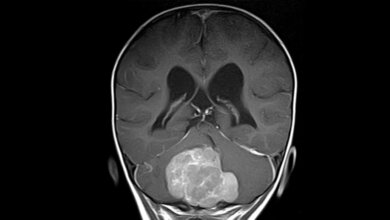

Doch auch bei der Diagnostik geht es mit Riesenschritten voran. Neben den neuen Möglichkeiten in der Bildgebung ist hier beispielsweise Liquid Biopsy ein Schlagwort. Die Nukleinsäureanalytik zum Nachweis von Tumorzellen und Tumor-DNA sorgt für Furore.